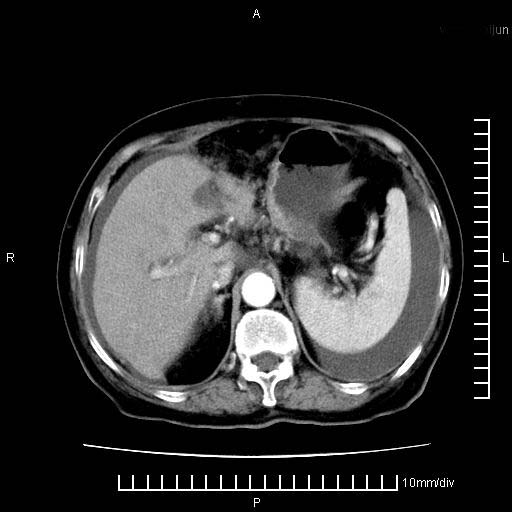

上腹疼痛月余,外院核磁诊断胰腺癌。现临床示右下腹可明显触及包块,可片子上怎么没有看到?

1。胰腺ca伴腹膜腔转移

2。肝左叶低密度灶,考虑转移可能

支持胰腺癌肝内转移,腹水改变。

1、考虑胰腺癌伴腹膜腔转移,胸腹水。

2、肝脏转移可能。

1)考虑胰腺癌并胰腺假性囊肿形成。2)肝内低密度灶,不排除转移。3)右肾盂积水。4)腹水。5)右侧胸腔积液并右肺下叶部分膨胀不全。

考虑胰腺ca伴腹膜腔转移、肝左叶转移、右肾积水。右胸腔积液。

考虑胰腺ca伴腹膜腔转移、肝左叶转移、右肾积水。右胸腔积液。支持